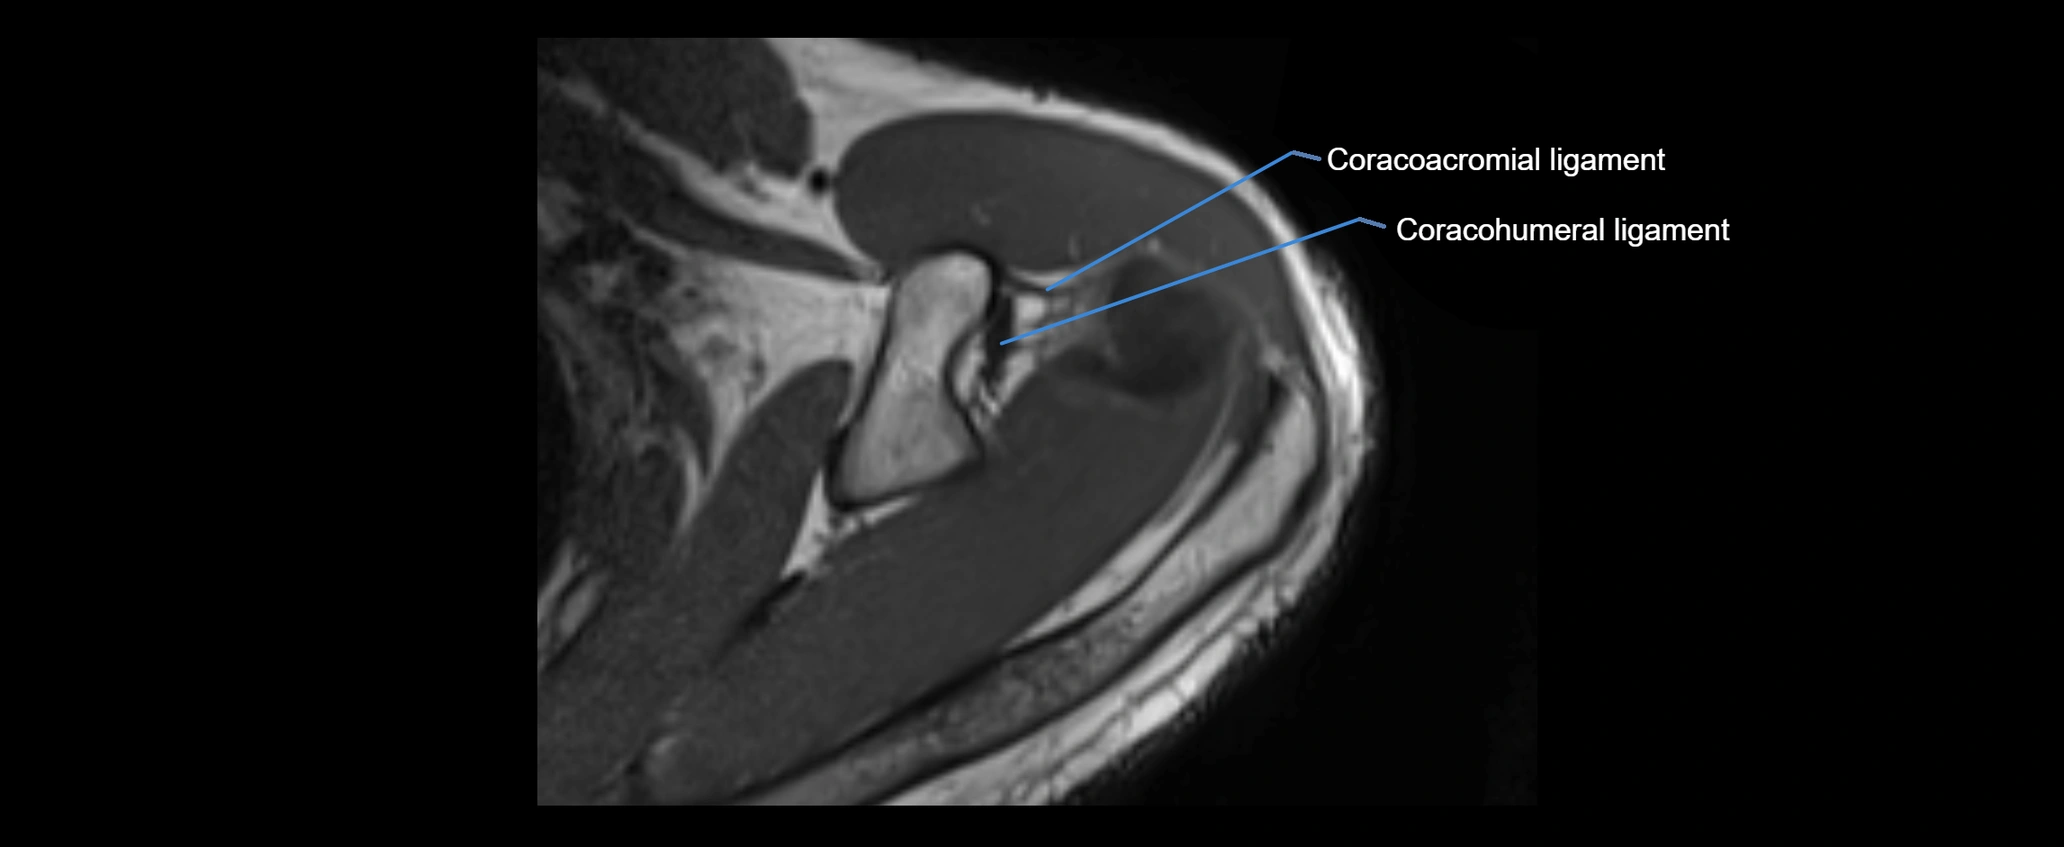

MRI images

image